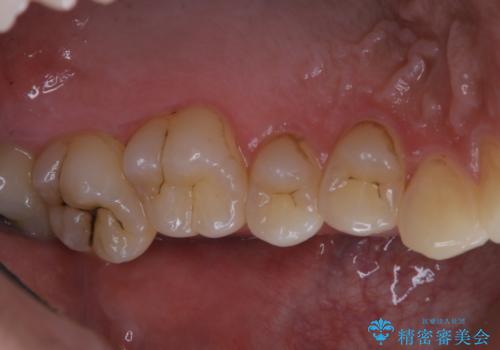

タバコによる着色をPMTCできれいな白い歯に

- タバコによる着色を綺麗にしたいとのことで来院されました。PMTC60分コースを行いました。